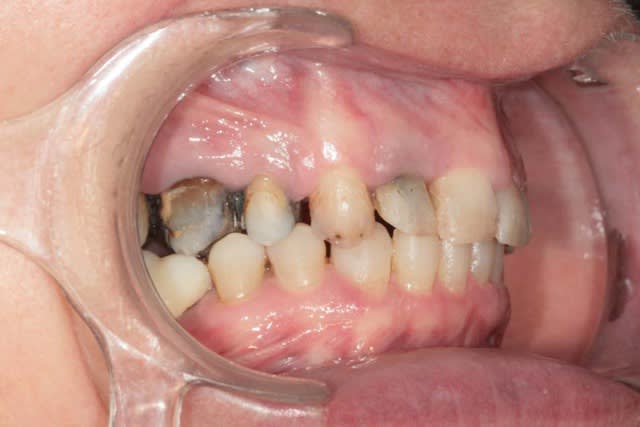

Récemment Céramik râlé, parce qu'il n'y avait pas de nouveau cas (esthétique je crois) à se mettre sous la dent. Je me jettes à l'eau avec ce dernier cas posé ce vendredi (y'a pas plus frais), une larme à l'oeil parce qu'il s'agit aussi du dernier gros cas dans mon cabinet que je quitte cette semaine pour rejoindre ma belle et nos p'tits bouts loin la bas dans le sud.

La patiente a un sourire très médiocre avec migration de plus en plus marqué du bloc incisivocanin sup. Comment l'aidez vous?